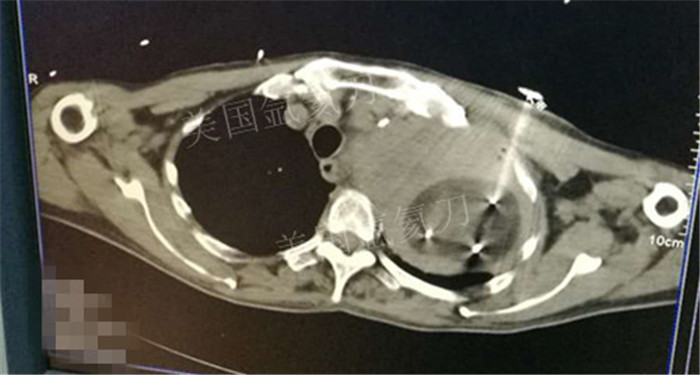

下一篇:氩氦冷冻治疗最大径8.2肿瘤,冰球最大径7.9